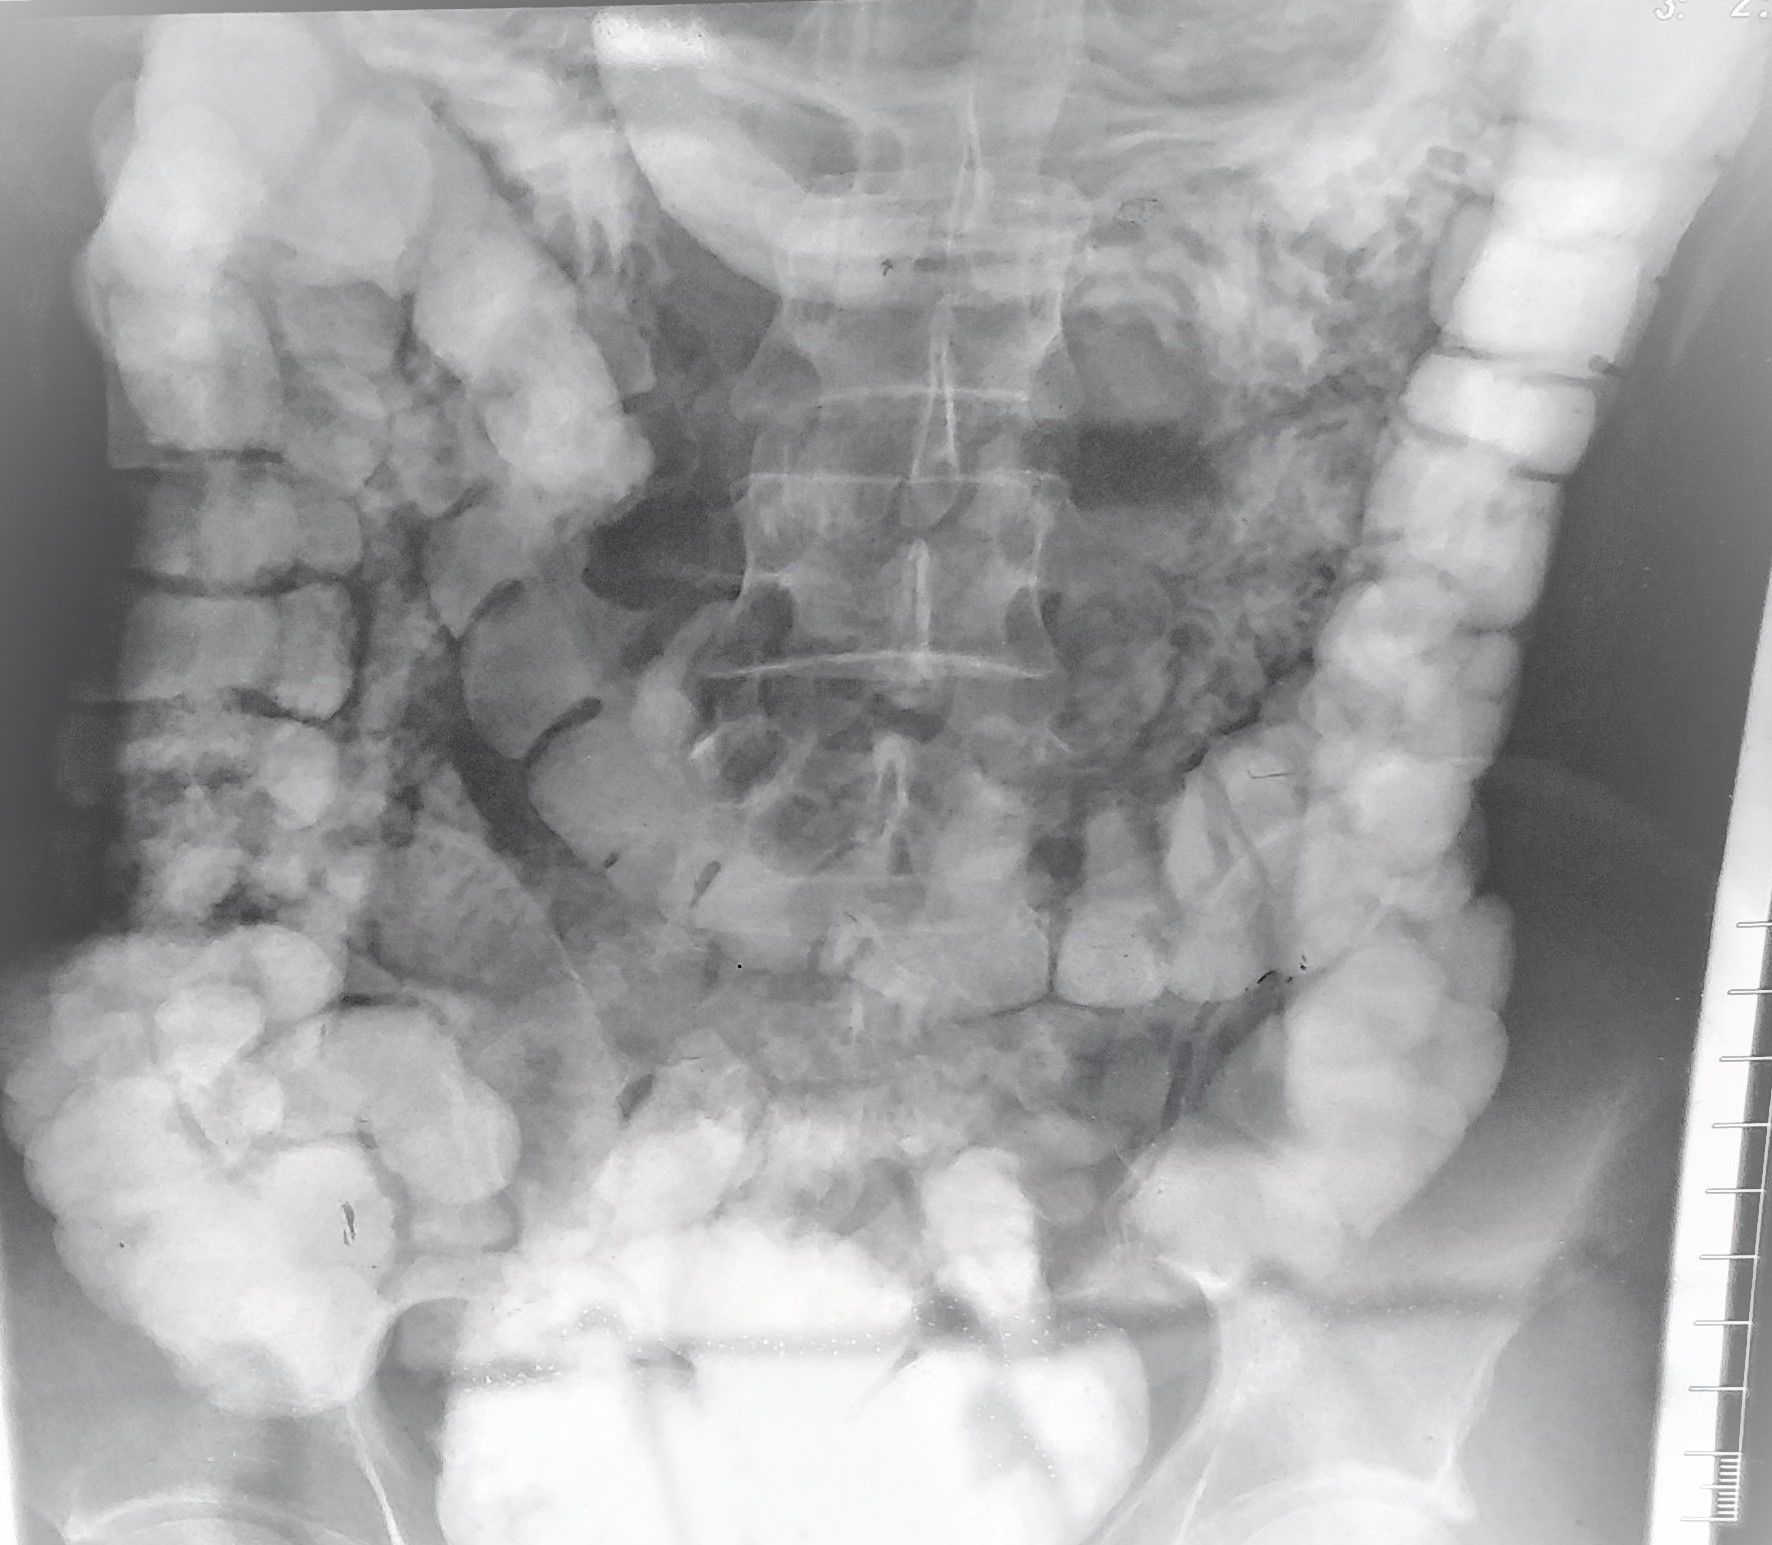

tortuous colon,is it serious?

What medicine can be used to promote intestinal motility, do I need surgery?